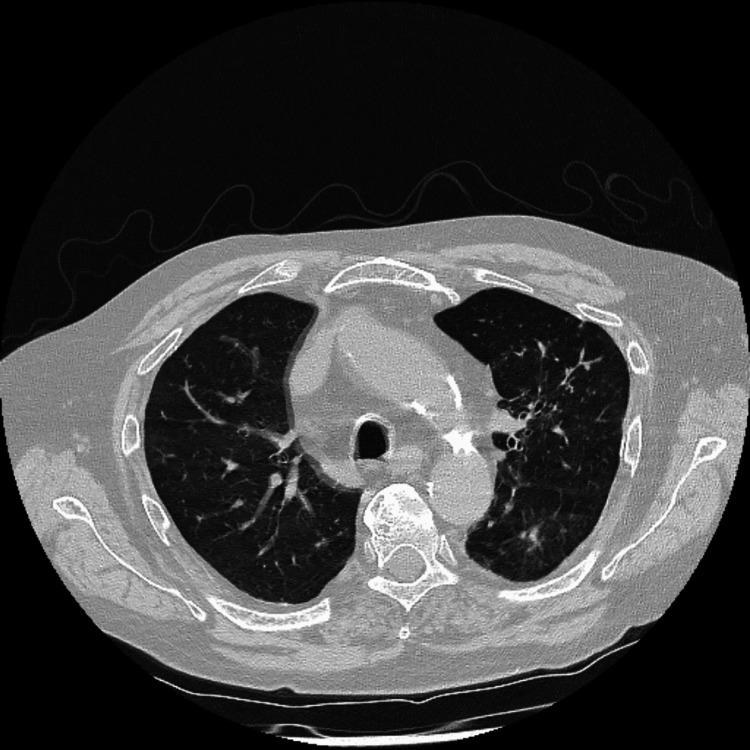

Anti-neutrophil cytoplasmic antibodies (ANCA)-associated vasculitides are a group of rare diseases that cause inflammation of small to medium vessels. They comprise granulomatosis with polyangiitis (GPA), microscopic polyangiitis (MPA), and eosinophilic granulomatosis with polyangiitis (EGPA). As the signs and symptoms are varied, the diagnosis of vasculitis is complex and challenging; however, there are type-specific clinical presentations that can be factored into the existing classification criteria. The difficulty faced in diagnosis is compounded due to ANCA being present in other chronic illnesses. While ANCA vasculitis may be triggered by infection, it is rarely associated with invasive aspergillosis. We present a case of proteinase 3 (PR3)-positive vasculitis with concurrent invasive aspergillosis in a 68-year-old male in whom both the clinical presentation and immunochemical picture were atypical. However, he responded well to treatment with immunosuppression. This report highlights the complexities in the diagnosis of vasculitis and the limitations of existing diagnosis and inclusion criteria.

抗中性粒细胞胞浆抗体(ANCA)相关血管炎是一组导致中小血管炎症的罕见疾病。它们包括肉芽肿性多血管炎(GPA)、显微镜下多血管炎(MPA)和嗜酸性肉芽肿性多血管炎(EGPA)。由于体征和症状各不相同,血管炎的诊断复杂且具有挑战性;然而,存在一些特定类型的临床表现可纳入现有的分类标准。由于ANCA也存在于其他慢性疾病中,诊断面临的困难更加复杂。虽然ANCA血管炎可能由感染引发,但它很少与侵袭性曲霉病相关。我们报告一例68岁男性患者,患有蛋白酶3(PR3)阳性血管炎并并发侵袭性曲霉病,其临床表现和免疫化学表现均不典型。然而,他对免疫抑制治疗反应良好。本报告强调了血管炎诊断的复杂性以及现有诊断和纳入标准的局限性。